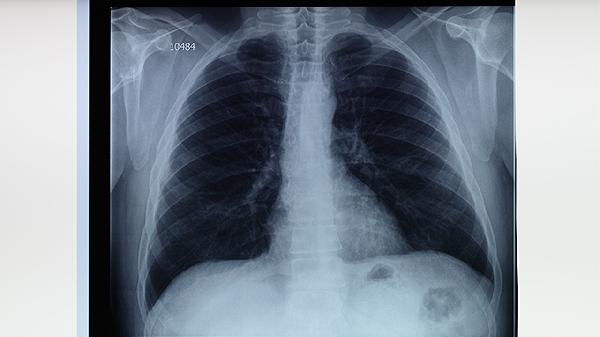

胸部X線或CT檢查可發(fā)現(xiàn)肺結(jié)核的典型表現(xiàn),如肺上葉尖后段或下葉背段的浸潤性病變、空洞形成等。影像學(xué)檢查對肺結(jié)核的診斷具有重要價值,尤其適用于痰檢陰性的患者。但需注意與其他肺部疾病如肺炎、肺癌等相鑒別。